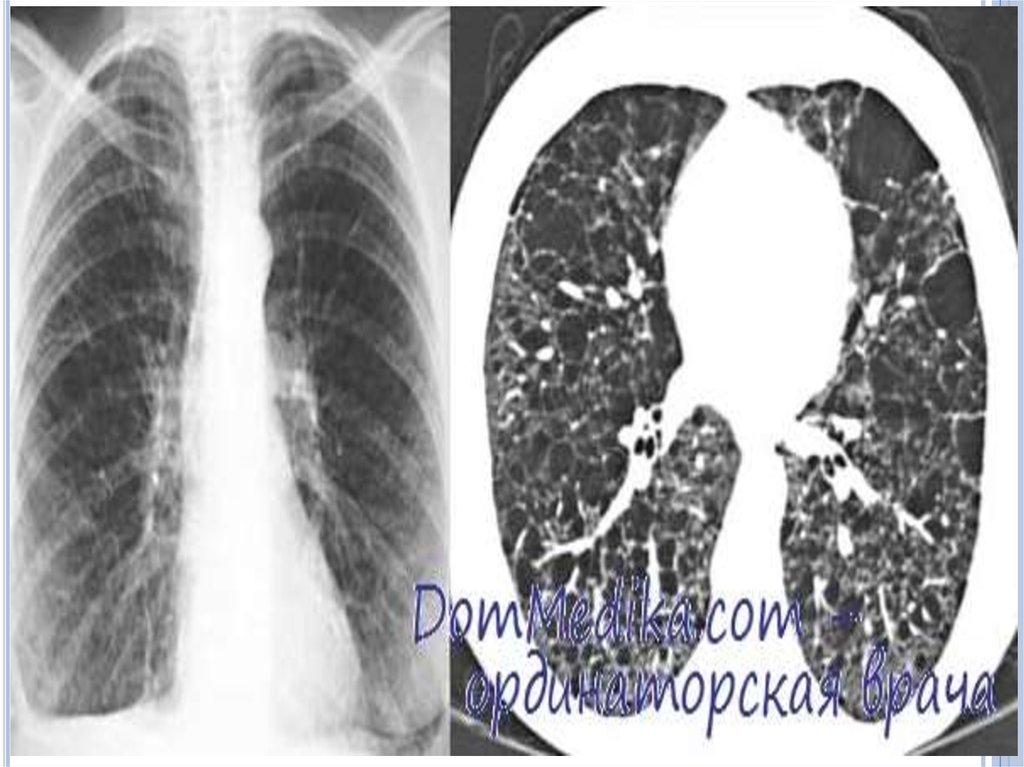

Инструментальные методы исследования

Рентгенологическое исследование легких - признаками

ЛАМ легких на обычных рентгенограммах грудной клетки

являются:

усиление легочного рисунка сетчатого характера;

увеличение объема легких.

Наиболее характерный морфологический признак ЛАМ кистозная трансформация легких, которая обычно выявляется

на компьютерных томограммах. Кисты бывают двух типов:

мелкие множественные типа «сотового легкого» и

крупные кисты, присущие буллезной эмфиземе.

Толщина стенки кисты не превышает 2 мм, причем стенка

кисты выявляется не всегда и не на всем протяжении.

Окружающая легочная ткань часто не изменена. Однако

сочетание фиброзных и кистозных изменений не

противоречит диагнозу ЛАМ. Таким образом,

рентгенологическая картина ЛАМ не патогномонична.

Ведущим рентгенологическим признаком этого заболевания

является образование множественных воздушных

11.

Компьютерная томография легких. Для ЛАМ

характерны множественные диффузные, хорошо очерченные

мелкие тонкостенные кисты. Кисты при этом заболевании

значительно отличаются от зон центрилобулярной эмфиземы

легких, которые не имеют четких границ и своих собственных

стенок, а также от фиброзирующего альвеолита, при котором

основные изменения расположены по периферии легких,

имеются поля фиброза и дезорганизации паренхимы легких,

а кисты расположены субплеврально и

характеризуются довольно толстыми стенками.

Данные компьютерной томографии настолько специфичны

для ЛАМ, что некоторые авторы для постановки точного

диагноза полагают достаточным заключение компьютерной

томографии (КТ) без проведения биопсии легких.